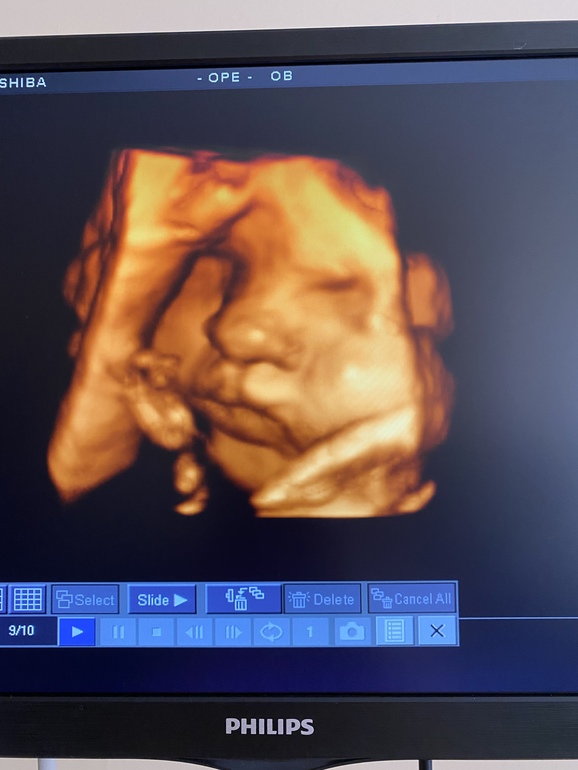

Сегодня ровно 35.Утром посетила жк,ВДМ как всегда отстает,идет на 32 недели.По узи как всегда опережаем-35,6 неделек ставит.Назначили последние анализы и отпустили.Спускаясь по ступенькам я почувствовала боль в промежности,как будто все кости таза решили разойтись разом,меня согнуло,не могла не ити,не стоять,начало резать все и человек как бур зашевелился ниже обычного.Думала все-рожаю,но где же воды думаю)))Меня усадили на лавочку ,чуть полегчало,но ити уже было тяжело до такси.Через час я была на плановом узи.Мы растем,щеки на нутрилоне отъели)

Стопа 7см!!)))мило😊Вес 2600Но!Головка опустилась низко(вот что это было).Говорит узистка не переживать,многие ходят и до пдр с низкой головкой,но и тут же сказала,быть готовой,носить бандажик и меньше напрягаться.Немного стало волнительно мне конечно.Еще и это чувство распирания теперь при ходьбе и давит между ног.Сумки в роддом почти собраны,малышковская полностью,моя по мелочи,детская готова,осталось только заправить кроватку,повесить пару картин.Надеюсь до 37 конечно дотянуть,не хотелось бы раньше рожать.Девчонки,кто доходил нормально с опущеной низко головкой?Самочувствие конечно «а ля за 60» кости ломит,все хрустит,тошнит,изжога сильная,бессонница)))🤣👌все как надо.Муж обувает,напяливает носки и штаны,так как после утренней ситуации с жк,я не могу сама это все делать,во первых больновато,во вторых боюсь,чтобы не выскочил парень😀Вообщем дай Боженька еще пару неделек нам🙏🏻И немножечко фоточек на память)наша моська,откормленная на смеси

Держу кулачки за вас с масиком))))))) такая моська сладкая на фото УЗИ😅❤️❤️❤️❤️❤️❤️❤️❤️❤️❤️❤️❤️

Голова опустилась по УЗИ ещё в 31+4)) так что бандаж и все будет ок 😉 щёчки прелесть

тьоо какой сладкий

обязательно сходите и вот лучше на 3 скрининге сделайте 4дешку.я вот делала до этого,ну как то не так,небыло еще щек таких)))

Какой пупс очаровательный)) нутрилонная душа 😄

Ирина

Какие же божественные щёки и губки!!!! И носик!!!!! Боже, какое сокровище!!! 😍😍😍😍😍😍😍😍😍😍😍😍😍